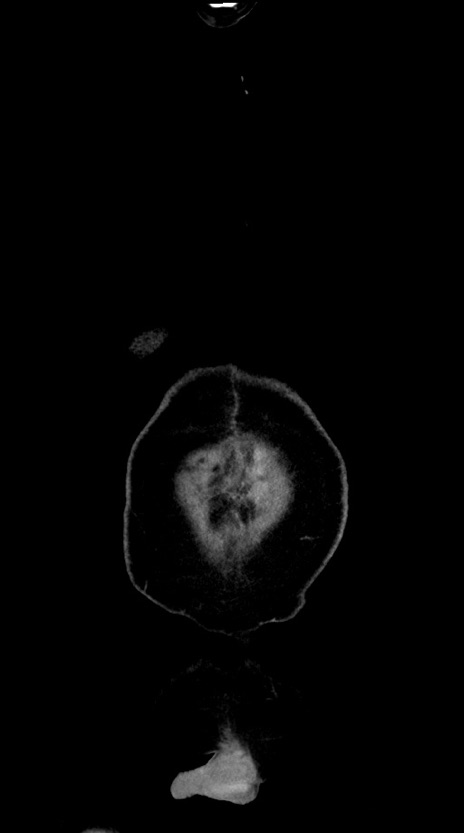

横断像

【症例】60歳代男性

【主訴】嘔吐

【現病歴】胃癌にて胃全摘後。食思不振が悪化し、夜中に嘔吐することがある。

【既往歴】胃癌、胃全摘、脾摘、胆摘後

【データ】WBC 5900、CRP 10.56